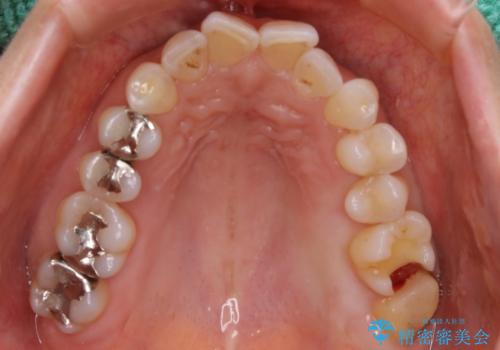

診断の結果、一番奥の歯は失活していたため精密根管治療から治療介入となりました。奥から2番目の歯にも大きな虫歯が認められたため、セラミックインレーによる補綴治療を行いました。 精密根管治療は患者様のご希望により、福本院長に行っていただきました。

今後は他の銀歯のやり替えも順次行っていくこととなりました。

セラミックは強い咬合力がかかると割れてしまうリスクがあります。今回のケースでは、歯を削る量をなるべく少なくしたいとの患者様の強い希望により、セラミックインレーを作製しました。破折してしまった場合には、歯牙全体を覆うクラウンにすることを十分説明し、ご理解いただいたうえで装着しております。